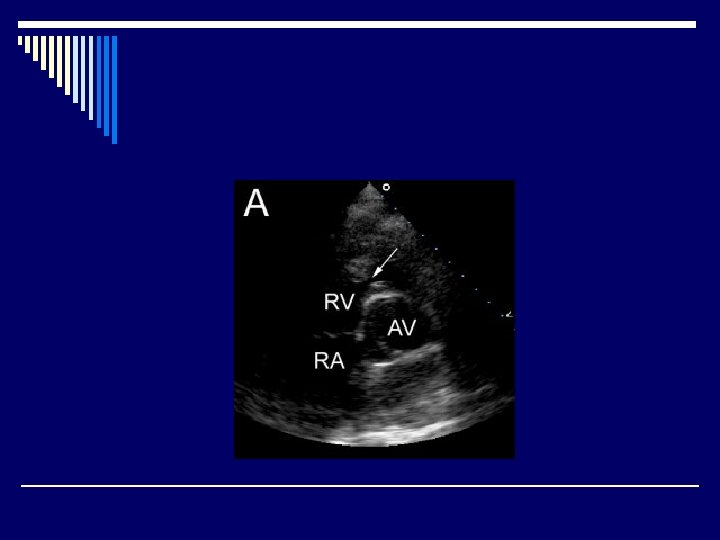

Echocardiography o. Diagnosis o. Decision-making o. Pre-and post-operative evaluation

TOF